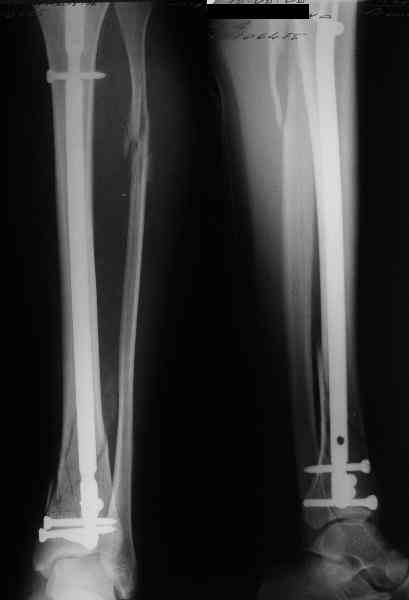

В приложении пример лечения аналогичного повреждения (плюс задний край).

Мы такие переломы закрыто штифтуем. Пластину больше смысла обсуждать, если требуется открытое восстановление суставной поверхности, костная пластика, в общем, если повреждение типа 33C3.

Выполнил MIPO предизогнутой метафизарной LCP